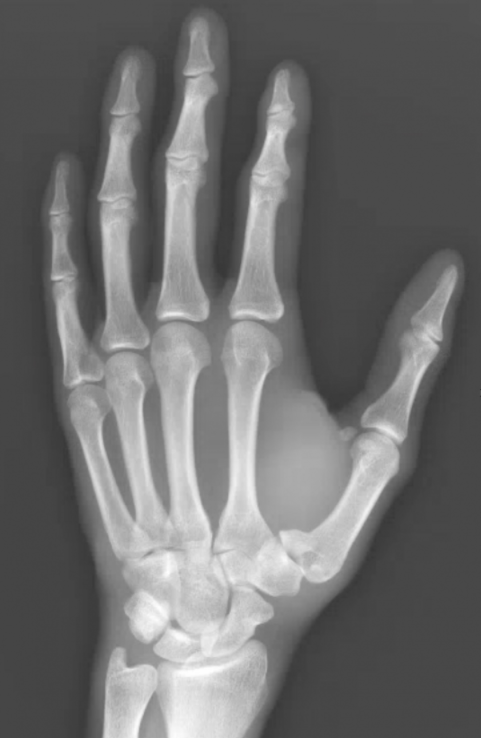

A 31 yo male presents with left thumb pain after a dirt bike crash. Patient is unable to move his left thumb and has tenderness at the base. An x-ray is shown below. What's the diagnosis? Scroll down for answer

Answer: Type I first metacarpal fracture (Bennett fracture)

- Type I, Bennett fracture: intra-articular fracture-dislocation/subluxation at the CMC joint